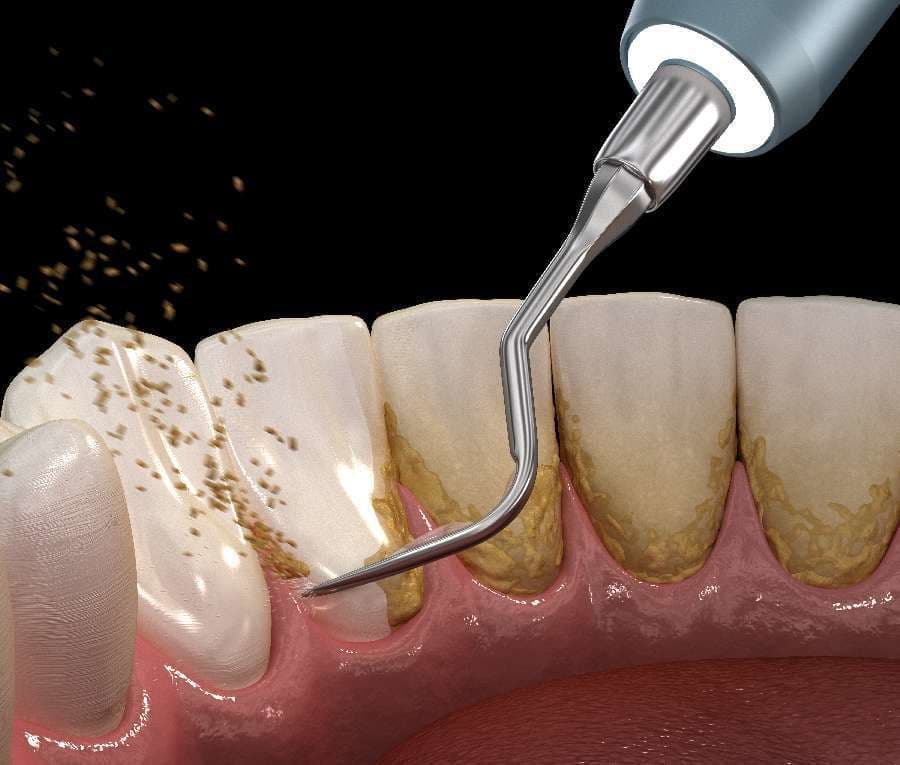

超音波スケーラー

超音波スケーラーは、主に歯肉縁上歯石のスケーリングを行なう際に使用します。

超音波スケーラーは、毎秒約25000~40000回の振動によって歯石を破壊し、除去します。

また、超音波スケーラーは歯石の除去以外にも、クラウンなどの補綴物の除去や根管洗浄にも使用されることがあります。